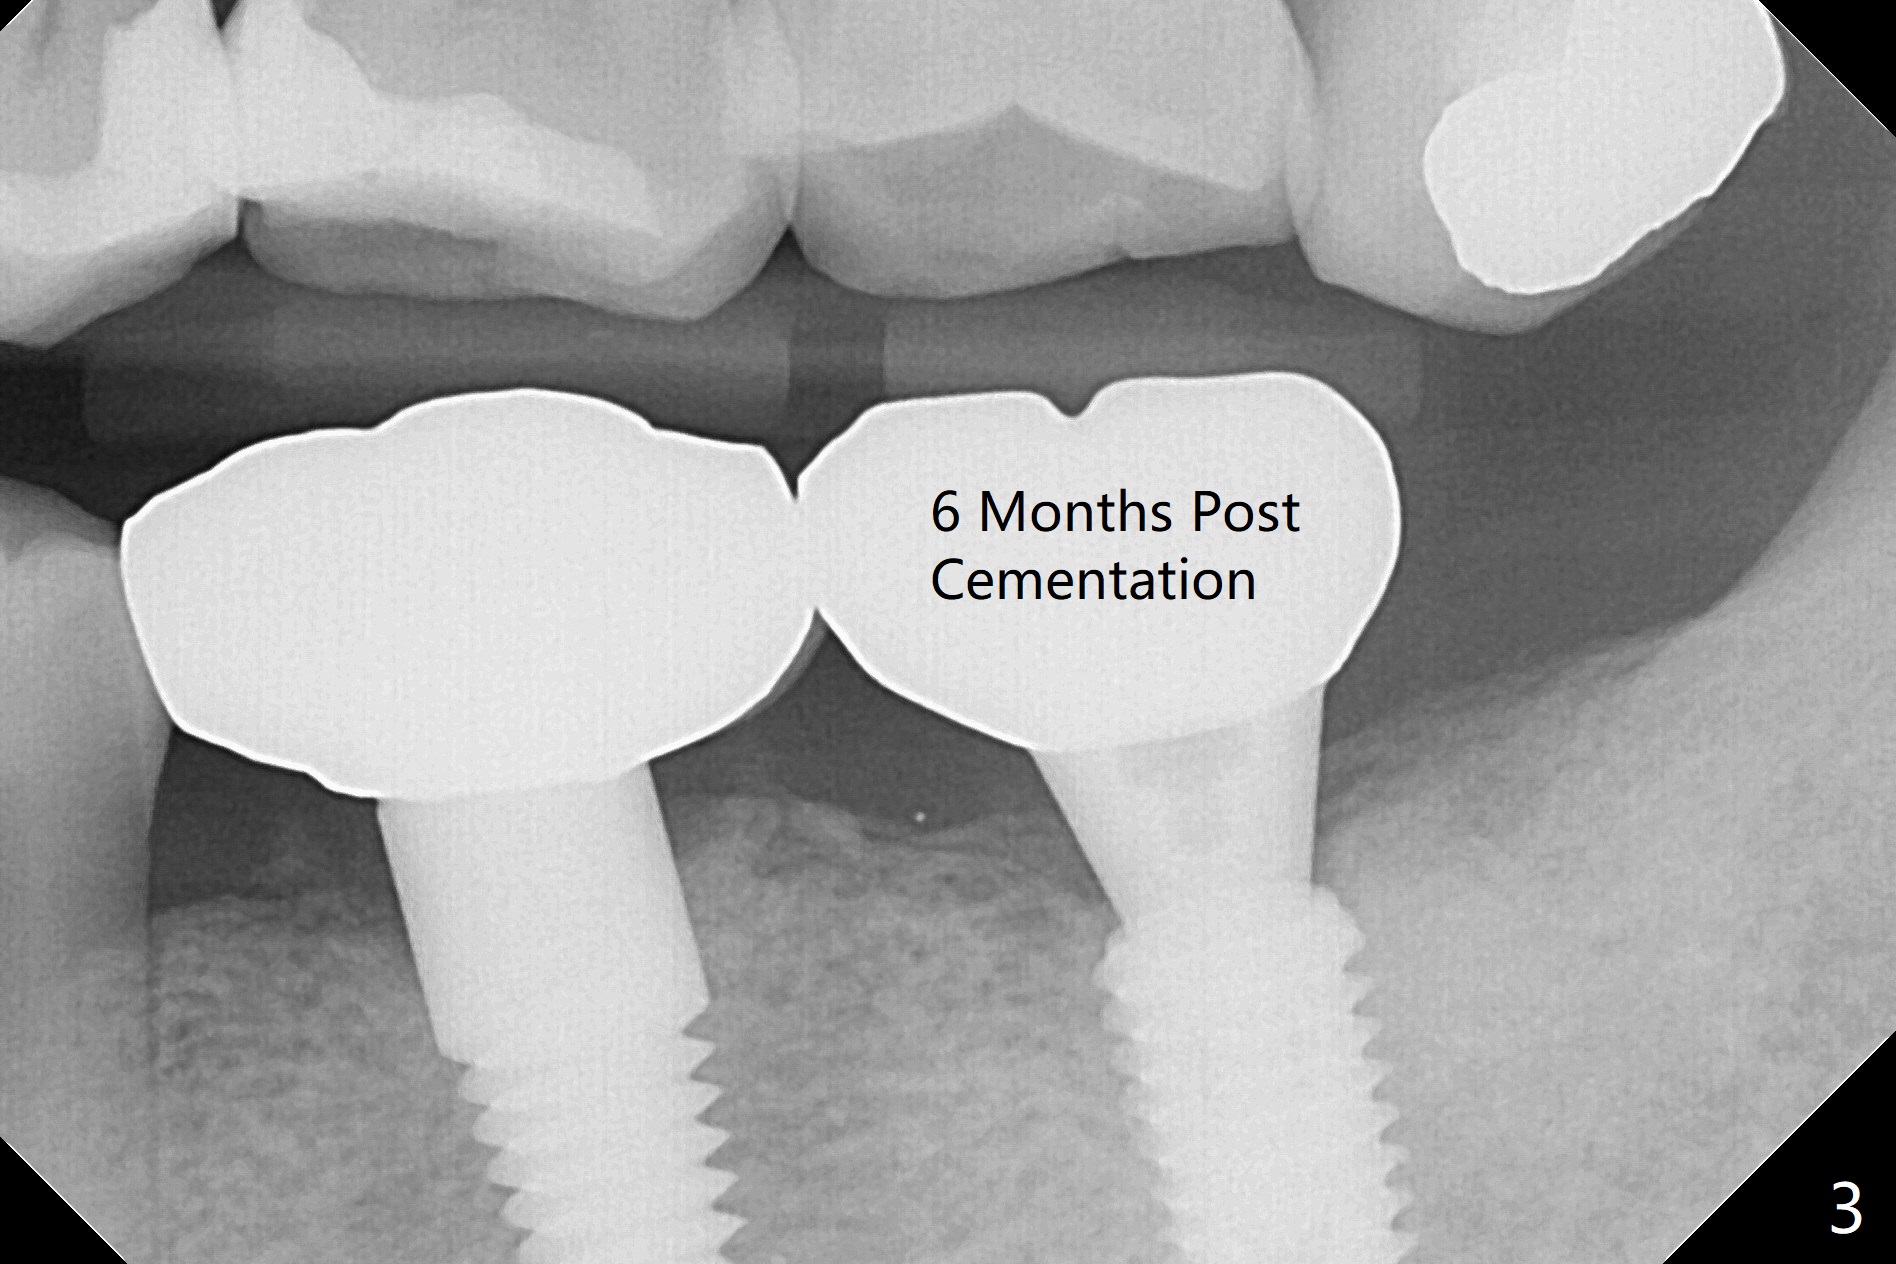

Crestal bone density increases 4.5 months postop (Fig.2).  There is no bone loss 6 months post cementation (Fig.3 (BW)).